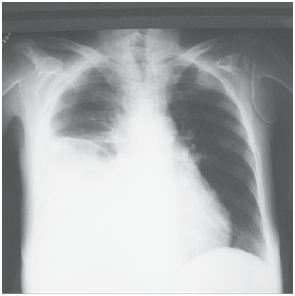

Mulher, 21 anos, apresenta febre, mialgia, cefaleia, dor retro-orbitária e náuseas há 6 dias. Exame físico: bom estado geral, corada e desidratada +/4+; bulhas rítmicas e normofonéticas, sem sopros; FC: 102 bpm; PA: 110 x 60 mmHg; murmúrio vesicular reduzido no terço inferior do hemitórax direito; FR = 26 ipm; abdome: ruídos presentes; dor moderada à palpação profunda em mesogástrio, sem visceromegalias; presença de edema +/4+, depressível em membros inferiores; presença de petéquias em ambas as pernas. Exames complementares: Hb = 13,9 g/dL; Ht = 42%; leucócitos = 2 900/mm3 (segmentados: 34%; linfócitos: 61%); plaquetas: 18 000/mm3; AST = 122 (VR < 32 U/L); ALT = 62 (VR < 31 U/L); pesquisa do antígeno NS1 para dengue negativo. Ultrassonografia de abdome: ascite de moderado volume. A radiografia de tórax encontra-se ilustrada a seguir.